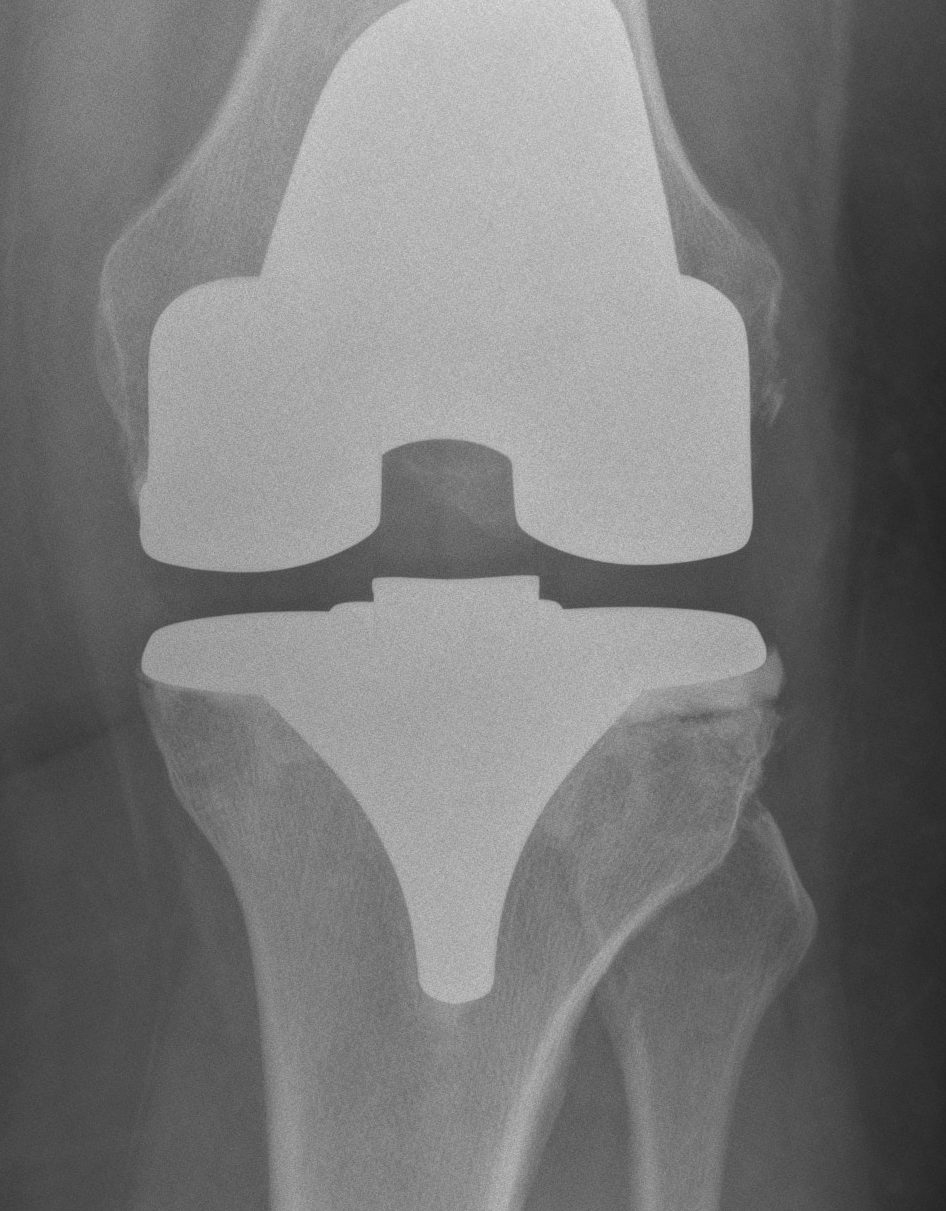

B. Standard +/- Revision TKR

2. Damaged Metaphysis

A One condyle

B Both

Management

A. Cement < 1cm

B. Augments < 2cm

C. Bone graft